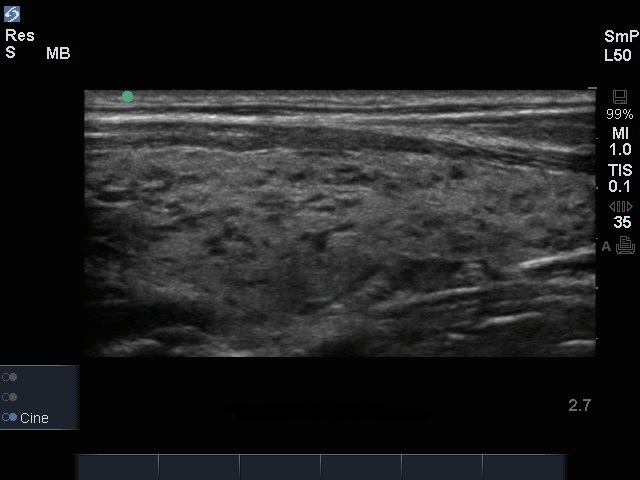

甲状腺異常サジタル画像